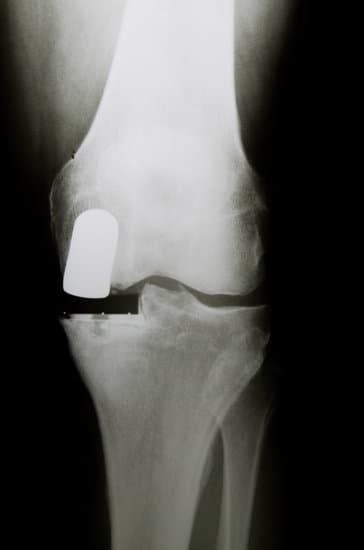

부분 인공관절 치환술 (Unicompartmental Knee Replacement)

부분 인공관절 치환술(UKA, Unicompartmental Knee Replacement)은 무릎 관절의 특정 부분에만 손상이 있는 경우 시행하는 수술로, 전체 인공관절 치환술(TKA)과 달리 손상된 부위만 교체하여 무릎 기능을 최대한 보존합니다.

엑스레이(X-ray)와 MRI로 관절 손상의 범위를 정확하게 평가합니다.

손상된 무릎의 부위를 절개하고, 마모된 연골과 뼈의 일부를 제거합니다.

해당 부위에 인공관절을 삽입하고 정렬을 조정합니다.